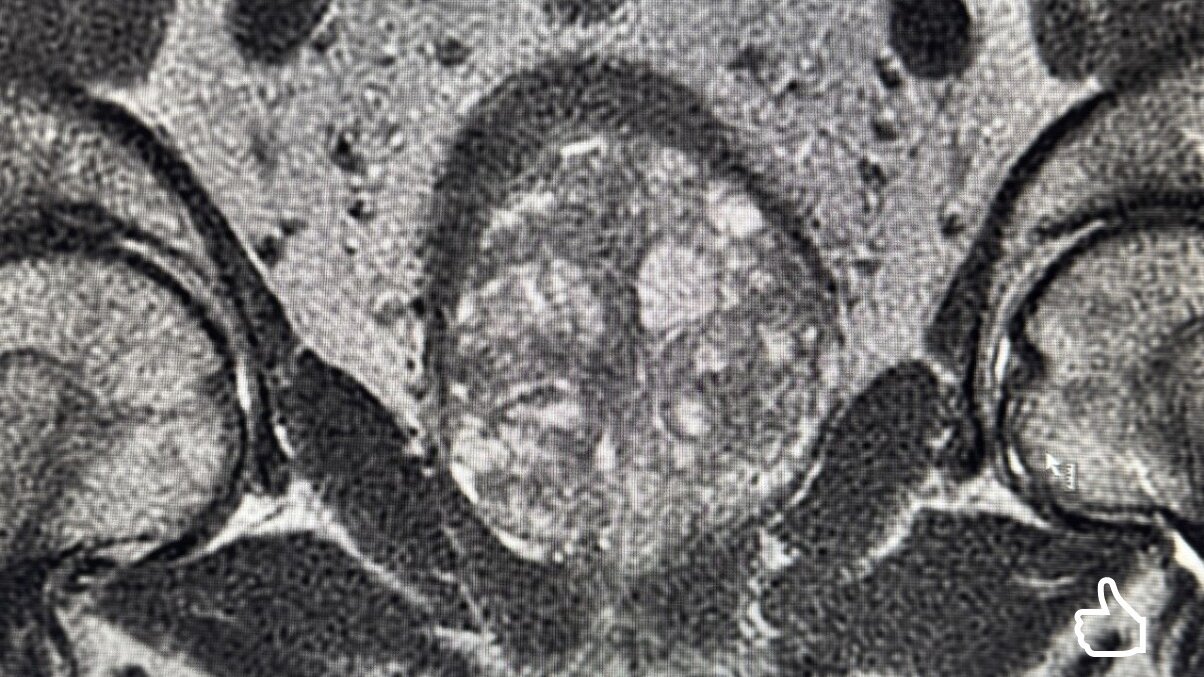

In der Klinik für Urologie des Klinikums werden regelmäßig hochkomplexe operative Eingriffe durchgeführt. Kurz vor den Osterfeiertagen führte der Chefarzt der Klinik für Urologie, Kinderurologie und urologische Onkologie, Arturo Rivera Mejia, eine besonders anspruchsvolle radikale Prostatektomie bei einer stark vergrößerten Prostata mit einem Gewicht von rund 200 Gramm durch.

Zum Vergleich: Das durchschnittliche Gewicht einer gesunden Prostata beträgt etwa 20 bis 25 Gramm und entspricht in etwa der Größe einer Walnuss. Die hier behandelte Prostata erreichte somit ein Vielfaches der üblichen Größe und stellte besondere Anforderungen an die operative Versorgung.

Gerade bei komplexen anatomischen Gegebenheiten ist eine präzise präoperative Planung entscheidend für den Behandlungserfolg. Detaillierte bildgebende Diagnostik, eine klar strukturierte Operationsstrategie sowie die enge Zusammenarbeit eines erfahrenen interdisziplinären OP-Teams bilden die Grundlage für ein sicheres und erfolgreiches Ergebnis.